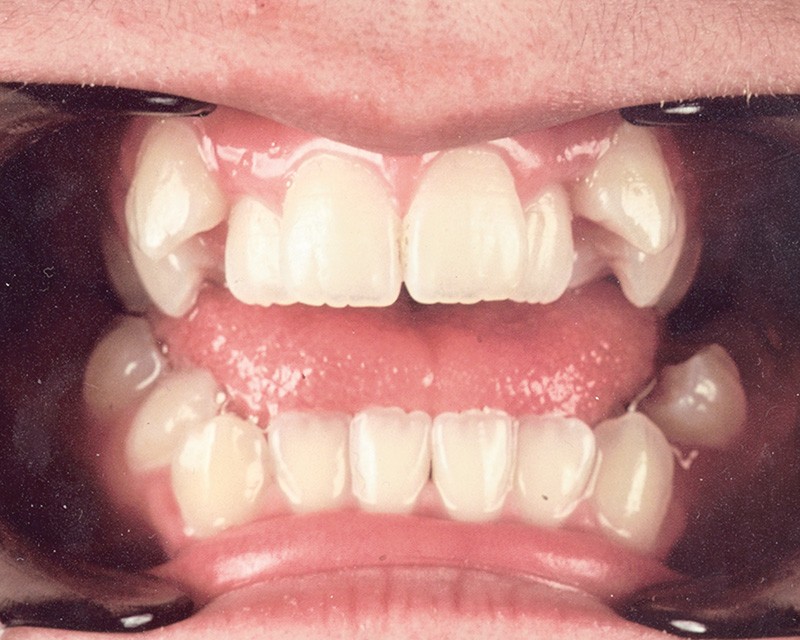

Sur le plan occlusal et dentaire, on observe une classe I molaire, une occlusion transversale en bout à bout à droite et inversée à gauche et une béance antérieure sévère s’étendant jusqu’aux molaires. Un encombrement est présent aux deux arcades avec des dystopies canines importantes (fig. 2).